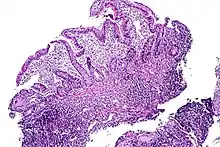

| Tissue of the ileum with inflammatory changes due to Crohn's disease | |